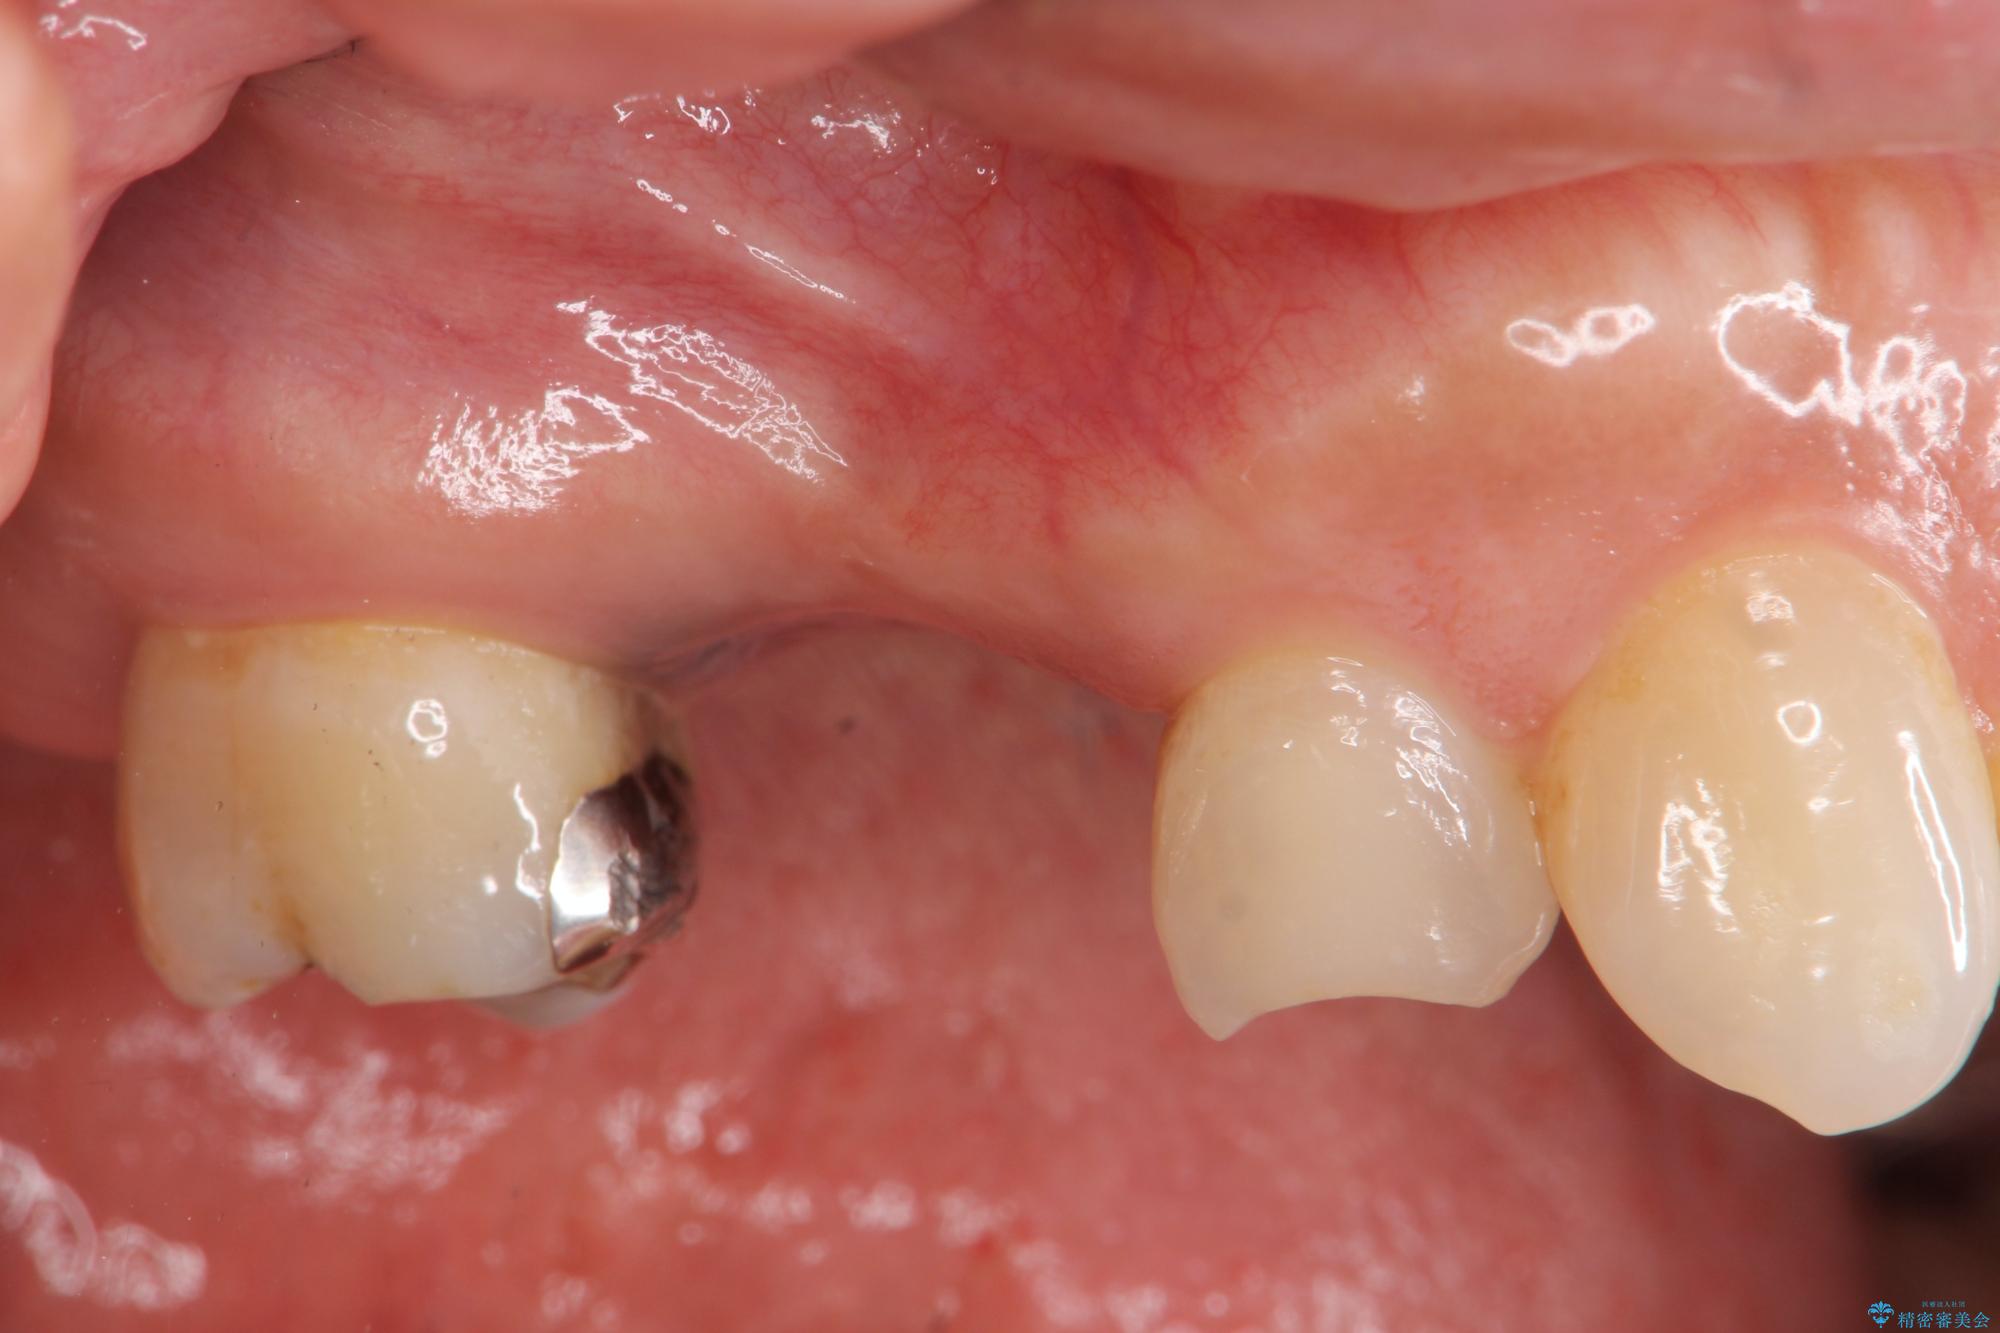

虫歯の悪化により奥歯を失った患者様です。 咬合機能の回復を求めてご相談にいらっしゃいました。

ブリッジ、インプラント、入れ歯による長短所のご説明を行い、インプラント治療を進めていくこととなりました。

インプラント治療を行ったことで前後の歯を削らずに咬合機能の回復をすることができ、大変ご満足いただけました。